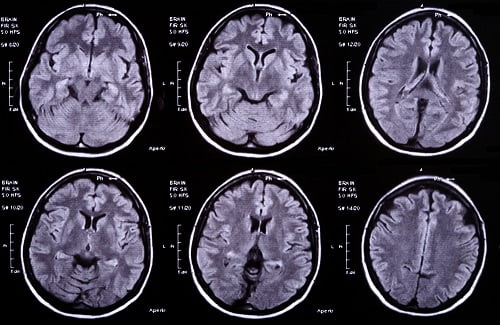

Так как симптомы, которыми характеризуется абсцесс мозга, не имеют определенной специфики и схожи с таковыми при других мозговых поражениях, важна дифференциальная диагностика абсцесса головного мозга. Обычно она заключается в проведении томографии с контрастом — МРТ или КТ.

- На ранних стадиях оптимальной является МРТ, так как КТ может «не заметить» воспаление ткани. На этапе инкапсуляции компьютерная томография становится информативной. Как правило, периферия очага на снимке принимает круглые очертания, так как контрастное вещество накапливается по контуру капсулы. На ранних этапах на МРТ-изображениях оценивается интенсивность сигнала энцефалитического очага.